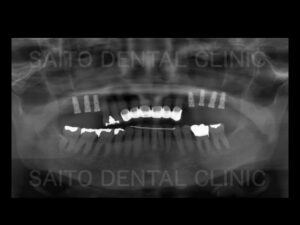

60代の女性の患者様です 治療前のお口の状態です。

全体的に歯がグラグラしており、特に前歯が前に出て、歯と歯の間にすき間が目立つ状態でした。

歯周病の進行により、上の奥歯もグラグラで噛むことができず残念ながら抜歯処置が必要な状態でした

その結果 前歯に負担が集中し歯の揺れやすき間が、さらに進行し、いずれ上の歯は全て抜ける可能性が

ありました